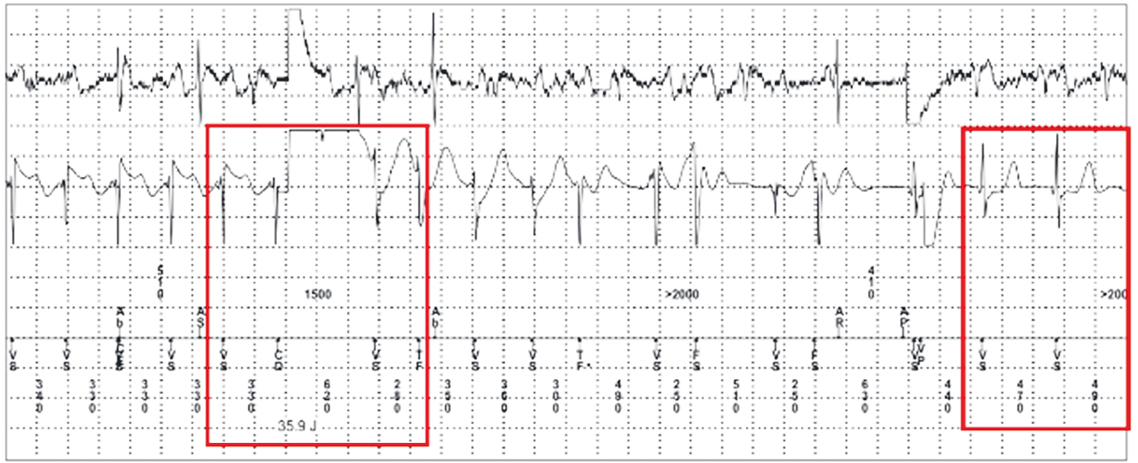

- One episode of sustained SM-VT with HR of 182–188 bpm; ATP therapy SM-VT with three attempts of ATP therapy without effect. After that, VT paroxysm was stopped by an ICD discharge (in accordance with the programmed algorithm).

Analysis of atp fragments for treatment of the episode of sustainable vt with hr of 182–188 BPM

The results of the analysis of fragments of ATP therapy demonstrated effective imposition of ATP pacing from the distal pole of the defibrillating electrode, with post-pacing interval at the time of ATP termination > VT cycle (but < 2 VT intervals), which indicated the entry of the ATP pacing sequence into the VT cycle (VT entrainment), but the inability of ATP therapy to arrest the paroxysm because of the inability to cause a bidirectional block in both directions in the vulnerable isthmus of VT. Thus, the ATP pacing cycle used was too long to achieve a critically short and effective refractory period (ERP) in the VT reentry cycle.

Revealing the cause: analysis of ATP therapy fragments in device memory

A fragment of the programming protocol with VT detection, ATP therapy, and subsequent cardioversion is presented.

Fig. 1. ICD detects VT with a cycle of 330 ms (a), delivers a series of ATP pacing (b), whereas the analysis of the ICD endogram indicates effective pacing, with post-pacing interval of 420 ms. ATP has entered a VT cycle which is at a distance of (420–330)/2 = 45 ms from the ICD stimulation electrode. However, VT persists at the same rate

Fig. 2. Owing to the lack of effect of ATP pacing, the ICD delivers a discharge and stops VT

Fig. 3. Summary of the detected and arrested VT episodes. The total duration from the onset of the paroxysm to its arrest was 1 min 27 s. The episode of SM-VT with HR of 182–188 bpm was detected by ICD. To stop the ICD-detected VT, three attempts were made to arrest VT using ATP, starting from a cycle of 88% of the detected VT cycle. Thus, for the VT cycle of 330 ms, the first sequence of ATP Burst-1 is plotted with a cycle of 330 × 0.88 = 290 ms. The imposition was effective, and there were no signs of loss of capture. ATP “entered a VT cycle” but did not stop VT and was not effective. As VT persists, the ICD delivers the next series of cycles 10 ms shorter, i.e. 280 ms and then 270 ms. The duration of the post-stimulation interval (return cycle 1 of VT) ranged from 410 to 420 ms, which indicated the effective imposition of ATP pacing and the absence of loss of capture. However, this cycle of ATP pacing was too long to induce VT arrest (by creating a blockade in both directions of the VT reentry chain). Owing to the lack of VT arrest, the ICD delivered a discharge and stopped VT